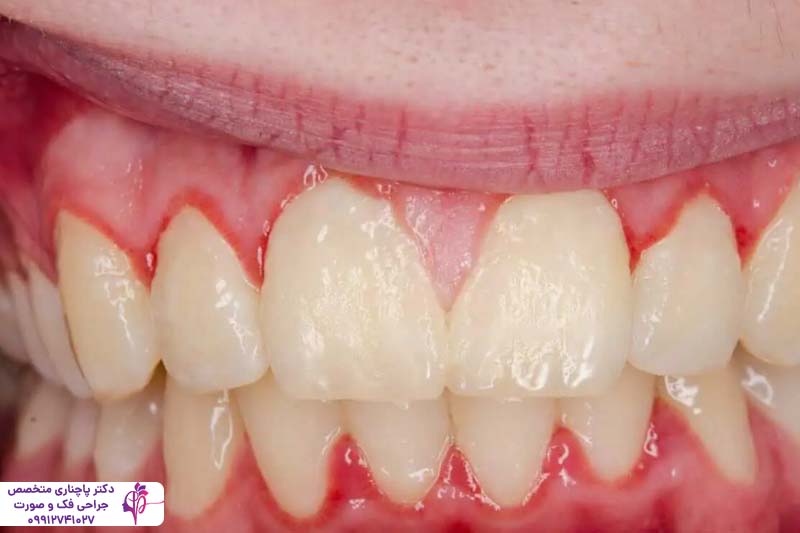

التهاب لثه (ژنژیویت)

التهاب لثه یا ژنژیویت خفیفترین شکل بیماری لثه است و به عنوان مرحله اولیه بیماری پریودنتال شناخته میشود. در این مرحله لایهای چسبناک از باکتریها و باقیمانده غذا روی صطح دندانها و در امتداد خط لثه جمع میشود. این پلاک اگر به طور منظم با مسواک زدن و نخ دندان پاک نشود، لثهها را تحریک میکند و منجر به التهاب میشود.

علائم التهاب لثه معمولا شامل قرمزی، تورم و گاهی خونریزی لثهها هنگام مسواک زدن یا استفاده از نخ دندان است. ژنژیویت هیچ دردی ندارد و به همین دلیل بسیاری از افراد اصلا متوجه این مشکل نمیشوند تا زمانی که به دندانپزشک مراجعه کنند. خوشبختانه این مشکل کاملا قابل درمان است و با رعایت بهداشت دهان و دندان، مسواک زدن منظم و استفاده از نخ دندان و در موارد شدیدتر دخالت دندان پزشک کاملا از بین میروند. اگر این مشکل در همین مرحله درمان نشود میتواند با شدیدتر شدن برای کاشت ایمپلنت دندان مشکلساز شود. درمان بیماریهای لثه قبل از ایمپلنت مثل ژنژیویت تضمین میکند که لثه برای حفظ پایه ایمپلنت کاملا شرایت مناسبی دارد.